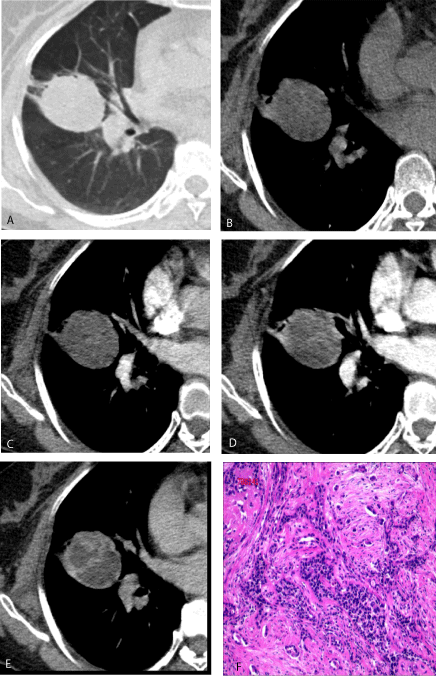

Chest CT scan showed a mass measuring 4.5 x 3.9 cm in the right lung middle lobe with inhomogeneous enhancement (Figure 1A-E). Based on these findings, an intrapulmonary tumor such as an inflammatory granuloma or lung cancer was suspected.

Histological findings showed proliferated atypical mesothelial cells and at least half consisted of irregular, dense, hyalinized collagen fibers. These tumor cells with consistent size and shape were arranged into various forms (tubular and papillary pattern eg.) (Figure 1F). Desmoplastic mesothelioma was suspected.

Figure 1: Ulcerative ungual exostosis of the big toe (the tumor is centrally developing, lifting and deforming the nail).